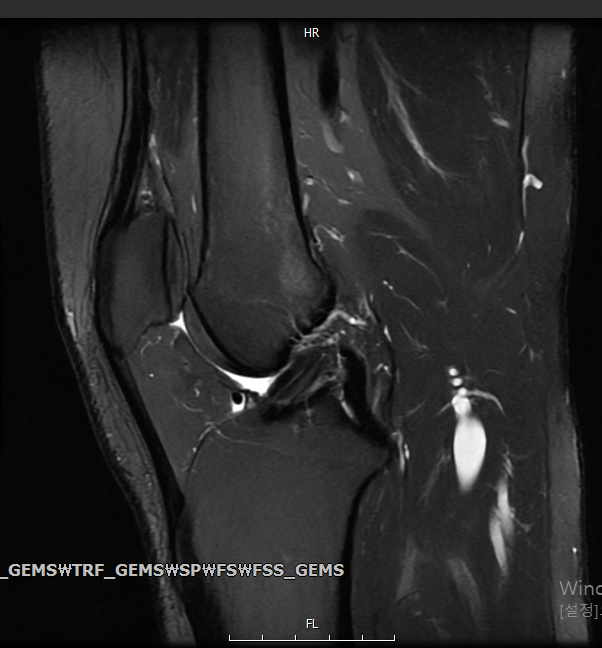

Mri를 찍었는데… 연골연화증인가요?

병원을 2번이나 번갈아가며 돌았는데도 별 의견 없이 진통제만 주셔서.... 믿을수가 없어 제가 그동안 공부 좀 해왔는데요, 관절 사이에 원래 저렇게 하얀색으로 차있으면 염증이라고 봤거든요. 슬개골부터 관절강까지 차있는거로 보아 무릎 연골 연화증인것 같은데... 심한 편인가요..? 프롤로 주사 맞으면 괜찮아지겠죠...?

• 2번 째 사진

현재 MRI영상만으로는 연골연화증을 의심할 수는 없으며, 관절사이의 물 또한 정상적인 관절액 정도로 볼 수 있을 것 같습니다.

올려준 MRI 사진에서 관절 사이에 하얗게 보이는건 물 입니다. 양도 많지 않고 정상적으로도 소량의 물은 있을수 있습니다.

연골연화증은 아닙니다. 애초에 올려주신 사진은 연골연화증을 판단하는데 쓰이는 사진도 아니네요. MRI가 쉬워보여도 제대로 판독하기까지 이론에 대한 공부와 수많은 케이스를 경험해보아야 합니다.

병원에서 그동안 별 의견없이 진통제만 주신 이유는 무릎 MRI사진에서 특이소견이 없어서인 것 같네요. 진통제 잘 드시면 될 것같습니다.